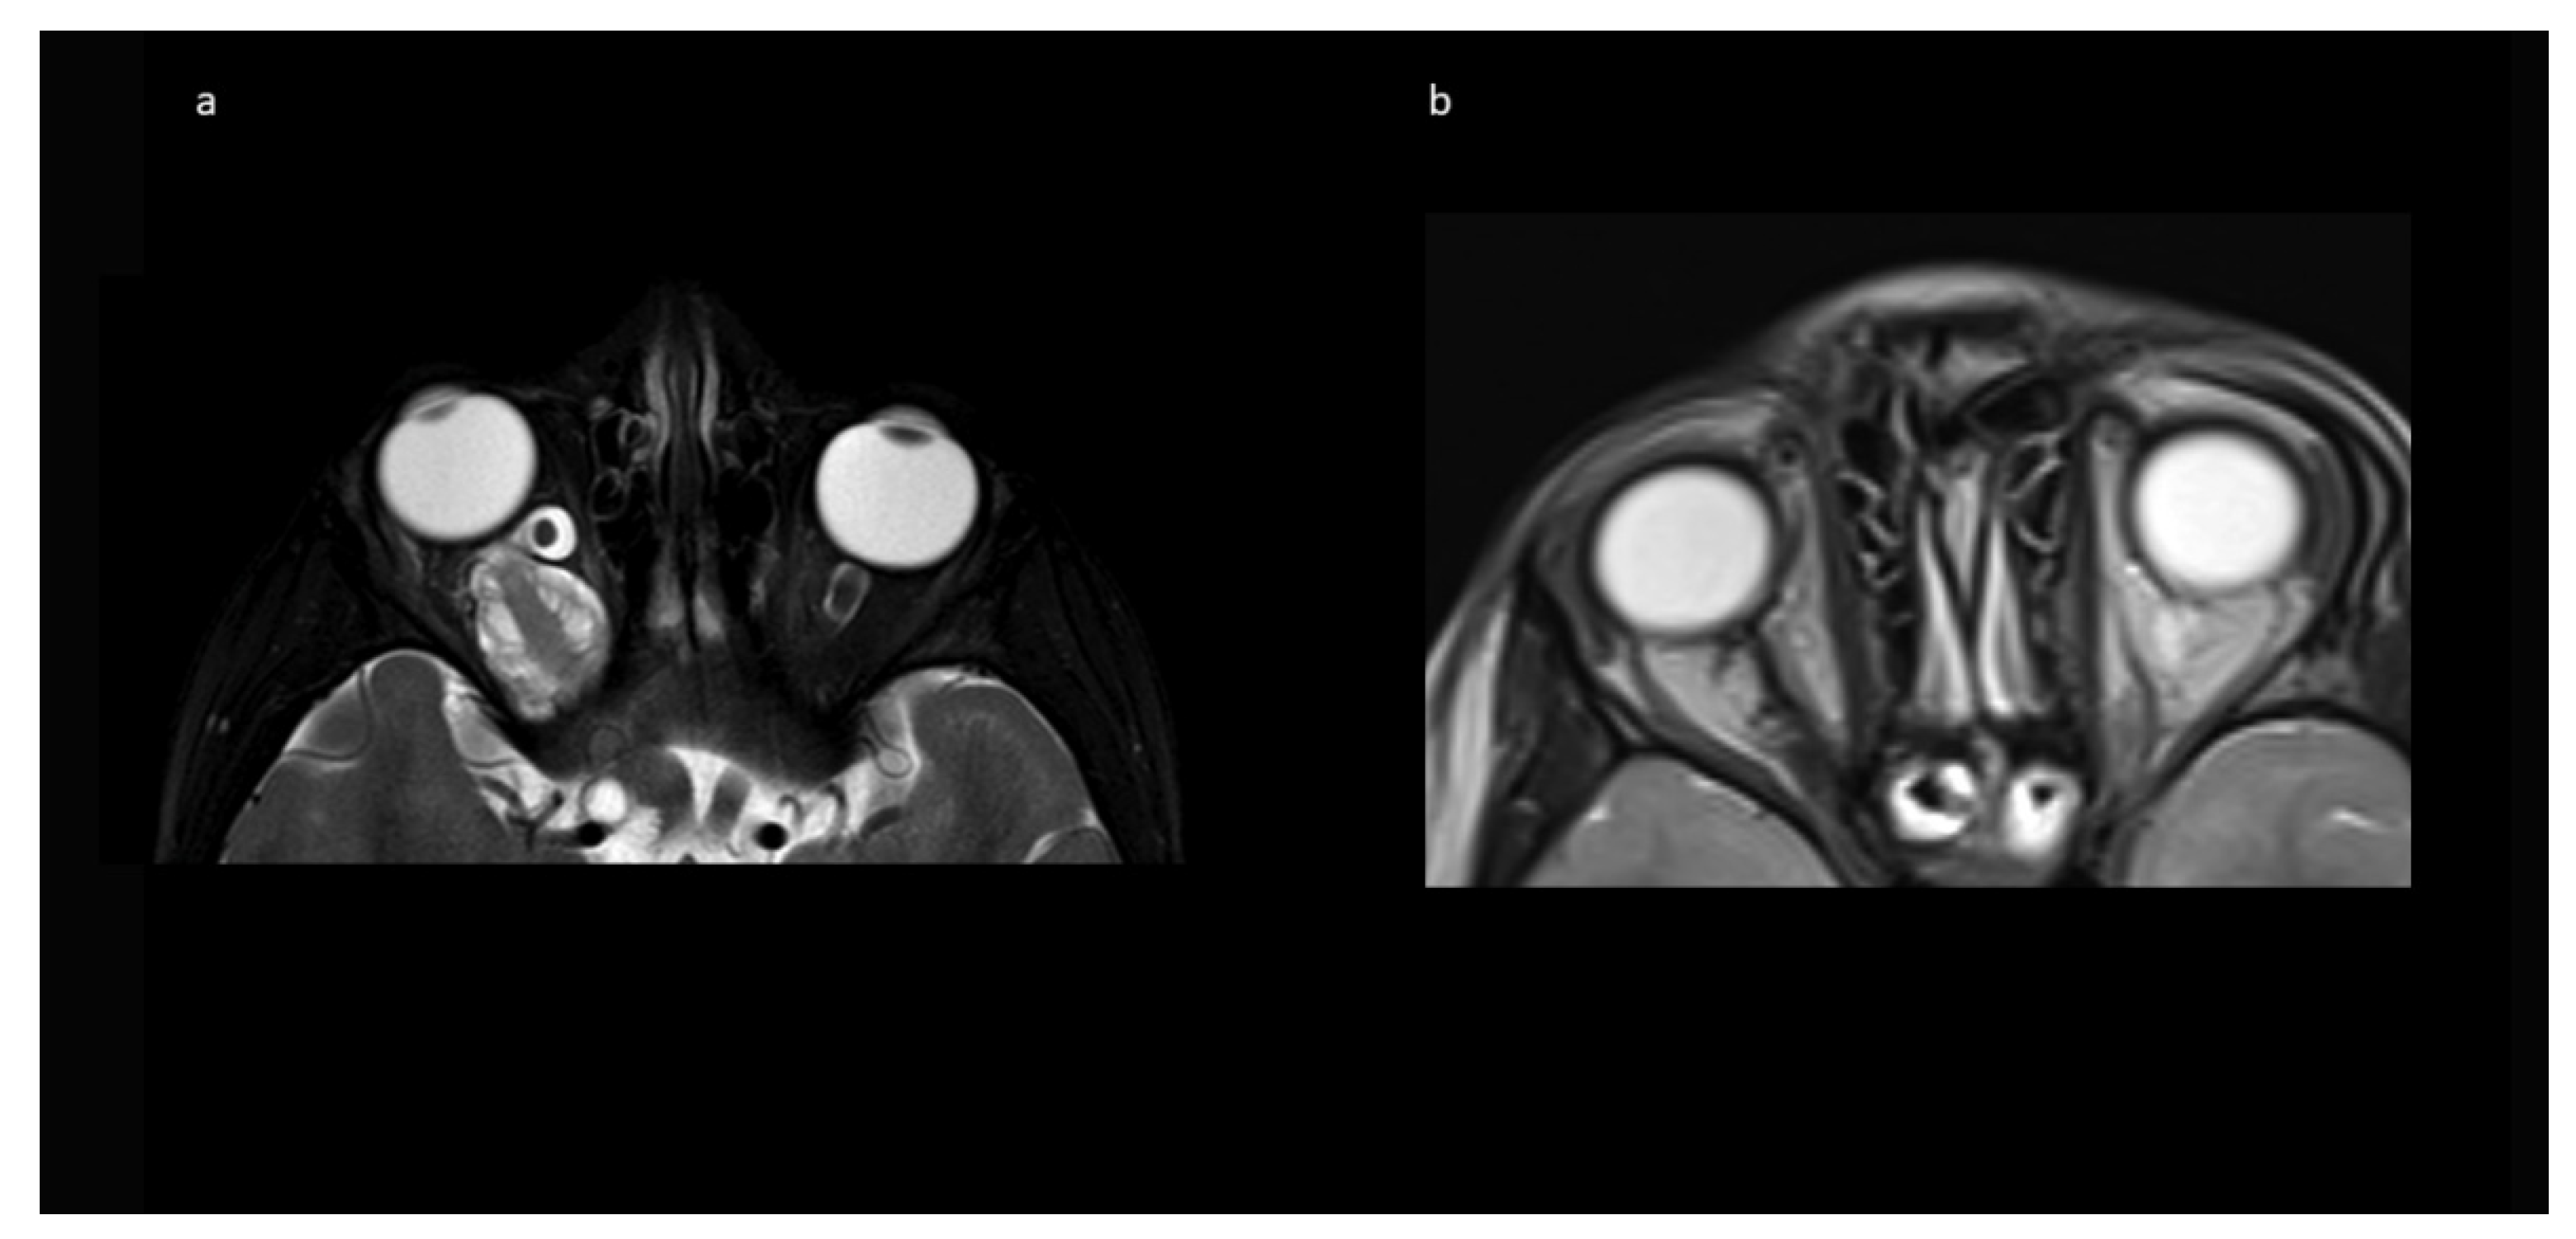

In Tuebingen (Group A), a fronto-temporal skin incision was used, followed by supraorbital craniotomy. After epidural exposition of the orbit, its roof is opened by osteotomy and the optic canal is unroofed with a diamond drill back to the dural fold. The anterior clinoid process is not drilled, and care is taken not to open the ethmoidal cells medial of the optic canal. After T-shape opening of the periorbital fascia, the frontal branch of the first trigeminal nerve and the superior rectus muscle/levator palpebrae muscle are dissected and retracted laterally, including the superior oculomotor branches entering the muscle from below, in order to expose the tumor. The abducens nerve is not encountered during this approach.

The nasociliary nerve crossing the optic nerve in the middle of the orbit and the trochlear nerve crossing close to the conus are identified to avoid injury during resection. Then, the dura of the optic nerve sheath covering the tumor is opened and an intradural tumor resection is performed, directed anteriorly following the nerve sheath, until the eye bulb is reached. Inside of the dura, no relevant neurovascular structures are encountered. Great care is taken not to injure the eye bulb at the level of optic nerve transection as close to the bulbus as possible. Then, the tumor is followed posteriorly within the optic nerve sheath towards the optic canal. The muscle attachment of the superior muscles at the orbital cone needs to be spared as well as injury to the visible trochlear nerve avoided. Then, the intradural resection is continued behind the muscle attachment within the optic canal towards the intracranial cavity until CSF comes from the intradural compartment. At this point, the dura is opened in a straight line at the level of the skull base; the intradural optic nerve, chiasm, and carotid artery are dissected; and the optic nerve is transected between the visible end of the tumor and chiasm. In the case of tumor extension close to or immediately at the chiasm, care must be taken not to enter the latter to avoid any injury of crossing fibers. The remaining tumor part in the junction area of the extradural optic canal and the intradural compartment just above the carotid and ophthalmic artery is carefully mobilized from its attachments using the intra- and extradural route and finally removed. The ophthalmic artery can be visualized in the first millimeter intradurally; the dissection at this transition zone has to be performed very carefully and without force, and this way injury to the artery is avoided. The artery can also be seen at the very beginning of the optic canal after tumor removal, but mainly runs behind the dural optic nerve sheath, and is thus not endangered there, just as the inferior oculomotor branches intraorbitally. The optic canal is plugged with muscle fixed with fibrin glue, and then the periorbital fascia is reconstructed with 6-0 sutures. The bone of the orbital roof is replaced and fixed with PDS sutures, and the dura closed thereafter. The craniotomy is refixed with PDS sutures in children below 15 years, otherwise titanium plates are used. Intraoperative photographs are provided in Figure 2.

Figure 2. Intraoperative microscopic view after left-sided craniotomy: (a) The optic roof was removed and the periorbita is visualized; the frontal nerve (V1) is seen under the retractor. (b) The optic canal is visualized extradurally. (c) Resection of the glioma in the optic nerve sheath intraorbitally. (d) Transection of the optic nerve prechiasmatically. (e) Combined intra- and extradural visualization of the optic canal and the intradural space medial to the carotid aretery. At the bottom of the optic canal, the beginning of the ophthalmic artery can be seen. (f) Reconstructed orbital roof.